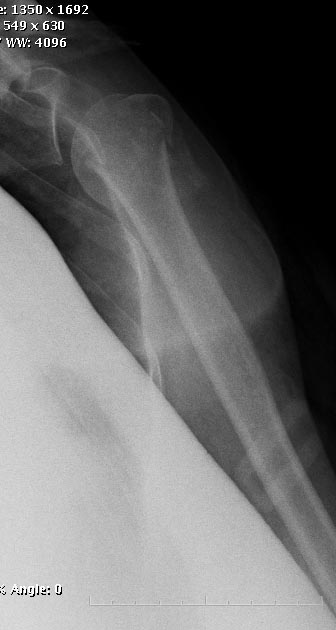

[Ortho] Перелом проксимального отдела плеча

> Гвоздь можно оставить убежденным нейлерам. Мы бы применили

Любой вид остеосинтеза нужно "оставить" тем, кто знает и умеет его

использовать. Когда чего-то не умеешь, легче всего выказать

пренебрежительное отношение - мол, это можно оставить им, мы-то

по-другому. НаучИтесь - понравится. Вот примерчик, операция закрыто

через 2 мес. после травмы.